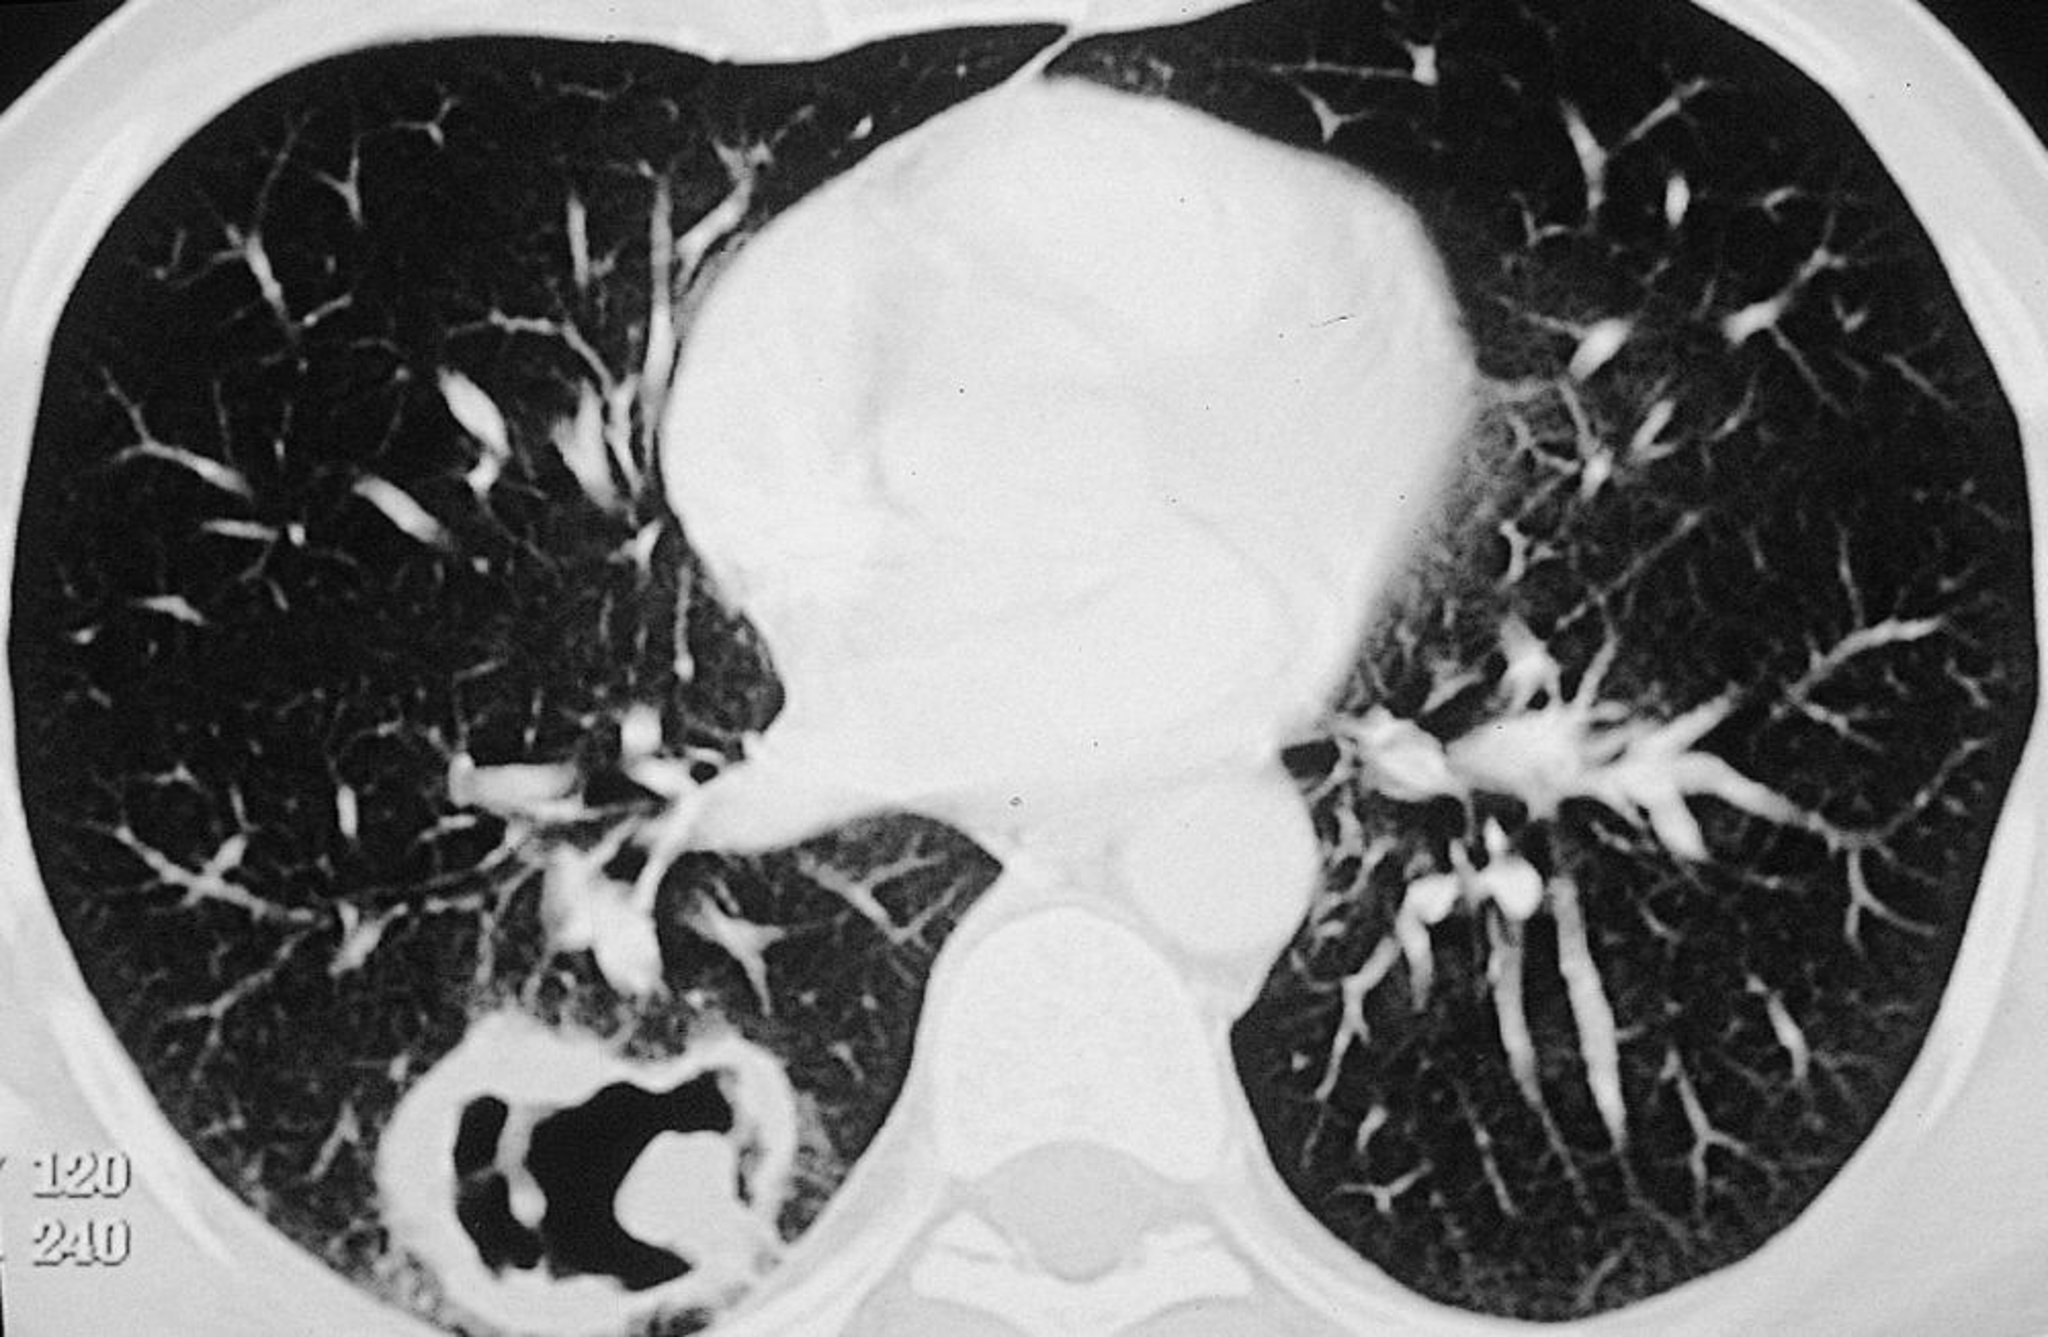

Tổn thương lớn ở phổi phải ở bệnh nhân bị u hạt với viêm đa mạch (GPA).